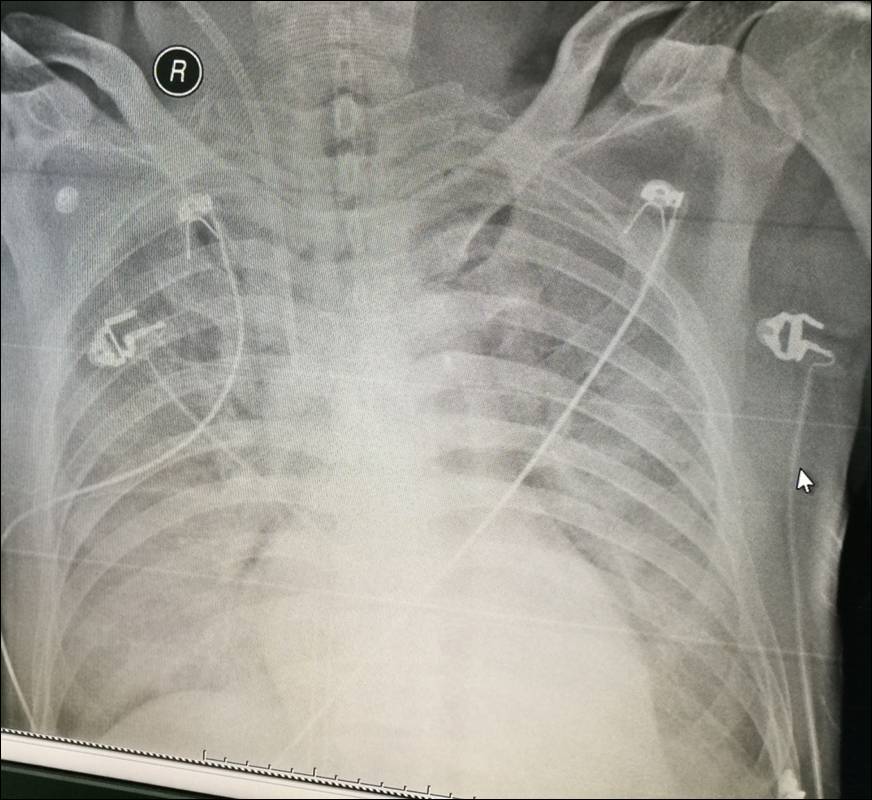

12-7 床边胸片

2016-12-8患者已恢复清醒状态,成功拔除气管插管,胃管,ECMO,撤除所有血管活性药物